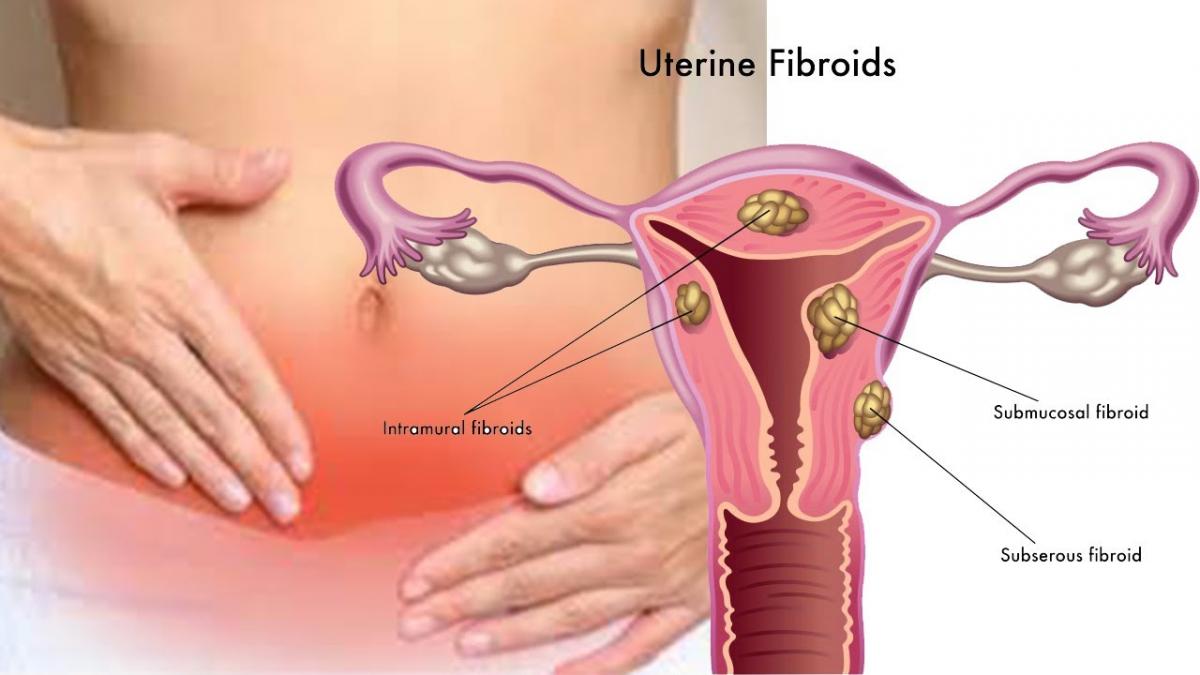

Embolizarea uterină

Embolizarea uterină este o metodă relativ nouă, nechirurgicală, de terapie a fibroamelor uterine. Ea constă în astuparea vaselor de…